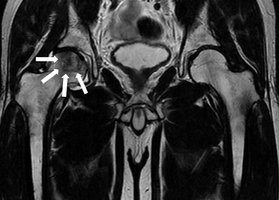

その次に画像検査をします。基本の画像検査はエックス線写真です。症状が進行しており大腿骨頭の陥没変形を認める場合はエックス線写真で容易に診断できます。しかし初期の段階で骨頭壊死の範囲が小さく、骨頭が変形していない場合はエックス線写真に異常が見られないことがあり、異常なしと判断されてしまうことがあります。早期診断を含めた最も有用な画像検査は磁気共鳴画像法(MRI)です。エックス線写真に異常を認めない段階でもMRIにより大腿骨頭壊死症を診断することが可能です。MRIにより大腿骨頭の陥没変形が生じる前から壊死が生じている範囲を詳細に把握することが可能です=写真=。